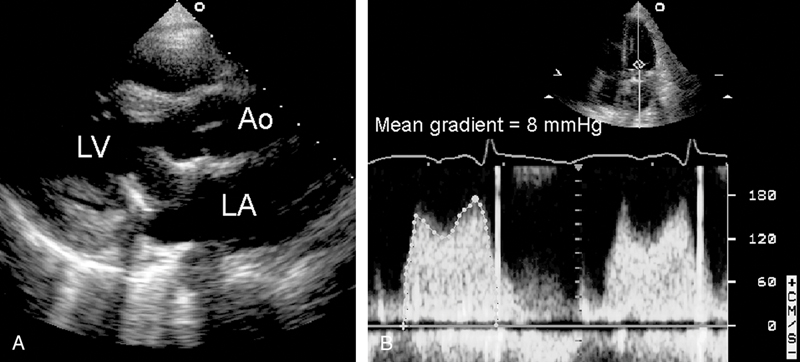

فحوصات تشخيصية لبعض امراض القلب والشرايين التاجية